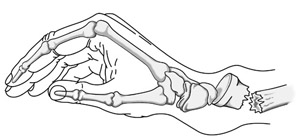

One of the most common distal radius fractures is a Colles fracture, in which the broken fragment of the radius tilts upward. This fracture was first described in 1814 by an Irish surgeon and anatomist, Abraham Colles -- hence the name "Colles" fracture.

A Colles fracture occurs when the broken end of the radius tilts upward.

This illustration shows some of the types of distal radius fractures.

Reproduced with permission from JF Sarwark, ed: Essentials of Musculoskeletal Care, ed 4. Rosemont, IL, American Academy of Orthopaedic Surgeons, 2010.